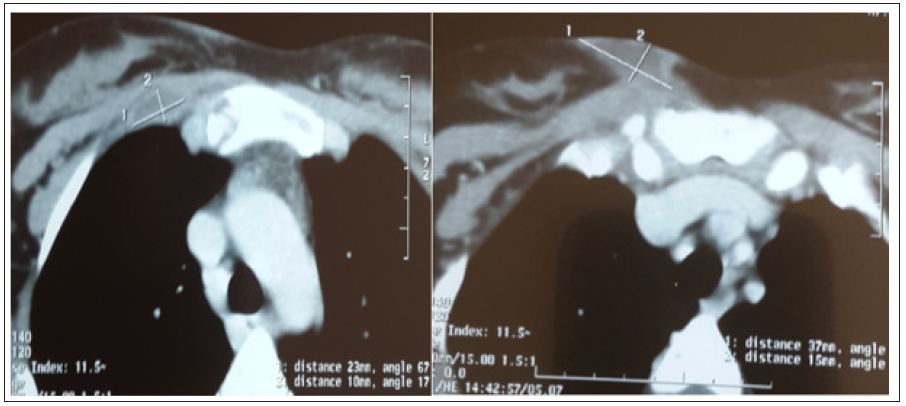

She is Miss S.A, aged 18, with no notable pathological history, including no tuberculosis or concept of tuberculous contusion, which has had a parasternal right swelling for a month. The examination of the swelling found a parasternal right mass just below the clavicle opposite the first intercostal space, painful on palpation, with redness, without cutaneous fistulization. An initial chest x-ray was requested returning without abnormality, in particular no lysis opposite, or associated parenchymatous involvement, with an infectious assessment negative made of a blood cell parameters and C- reactive protein, A thoracic computed tomography was performed objectifying an osteolytic lesion with intraosseous sequestration at the right super-lateral part of the sternum (Figure 1), associated with infiltration of the soft tissues and two abscesses, the first at right intercostal muscle level, and the second in the anterior parietal area (Figure 2). Flattening of the swelling was performed in the patient, with bacteriological and histological samples of the abscess. The direct examination and the culture of the pus came back negative. However, the molecular study of the collection by GeneXpert objectified a tuberculosis. The anatomopathological study revealed a granulomatous lesion, but without caseous necrosis. The patient was put on antibacillary treatment with good clinical progress.

Figure 2: Presence of two parietal abscesses, one at the level of the right intercostal muscle, and the second at the anterior parietal level.